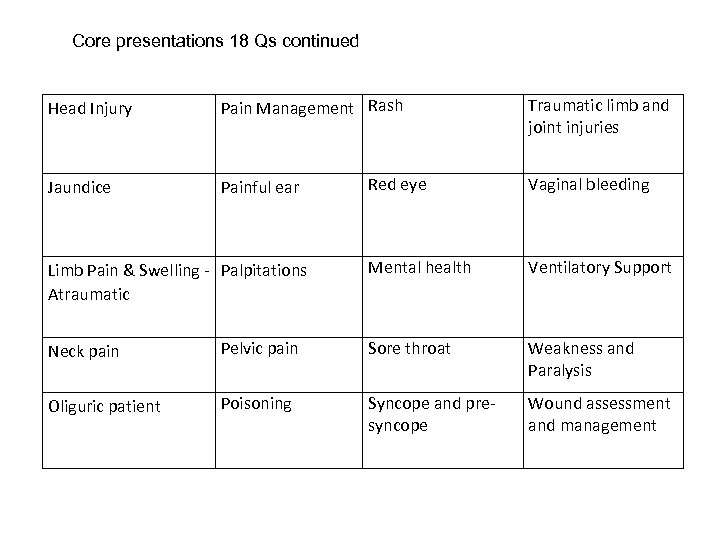

Core presentations 18 Qs continued Head Injury Pain Management Rash Jaundice Painful ear Limb Pain & Swelling - Palpitations Atraumatic Traumatic limb and joint injuries Red eye Vaginal bleeding Mental health Ventilatory Support Neck pain Pelvic pain Sore throat Weakness and Paralysis Oliguric patient Poisoning Syncope and presyncope Wound assessment and management